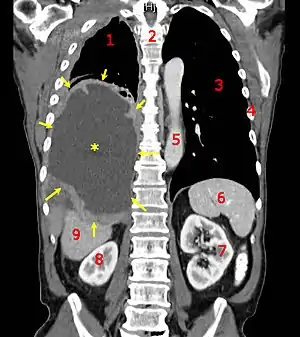

![]() | |

| CT scan showing a left sided mesothelioma with an enlarged mediastinal lymph node | |